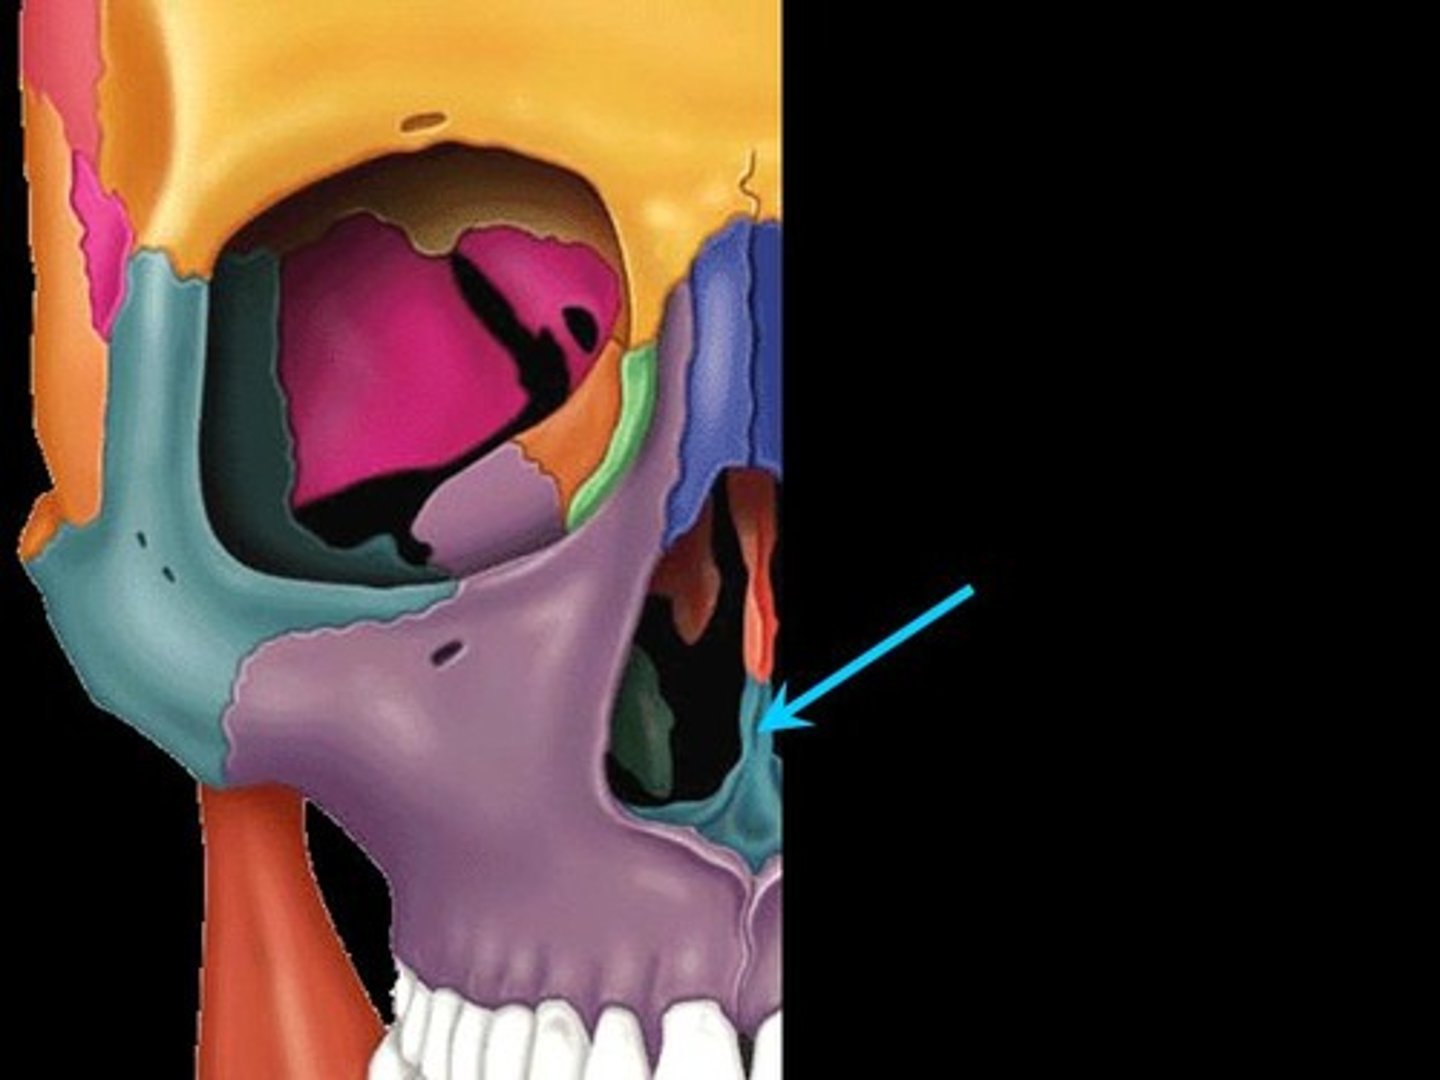

Inferior orbital fissure

Infraorbital foramen